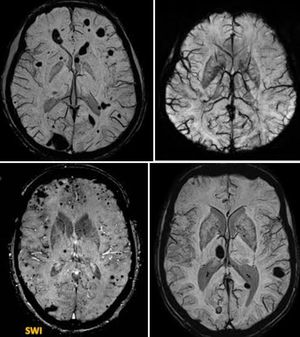

Susceptibility-weighted imaging (SWI) is a neuroimaging technique, which uses tissues magnetic susceptibility differences to generate a unique contrast, different from that of proton density (PD), T1, T2, and T2*. SWI uses a fully flow/velocity compensated, RF spoiled, high-resolution, three-dimensional (3D) gradient recalled echo (GRE) scan. Both the magnitude and phase images are saved. The phase image is high pass (HP) filtered to remove unwanted artifacts (background field inhomogeneities caused by air-tissue interfaces and main magnetic field effects). The magnitude image is then combined with the HP filtered phase image to create an enhanced contrast magnitude image referred to as the susceptibility weighted image (SWI). It is also common to create minimum intensity projections (minIP) over 8 to 10 mm to better visualize vein connectivity.